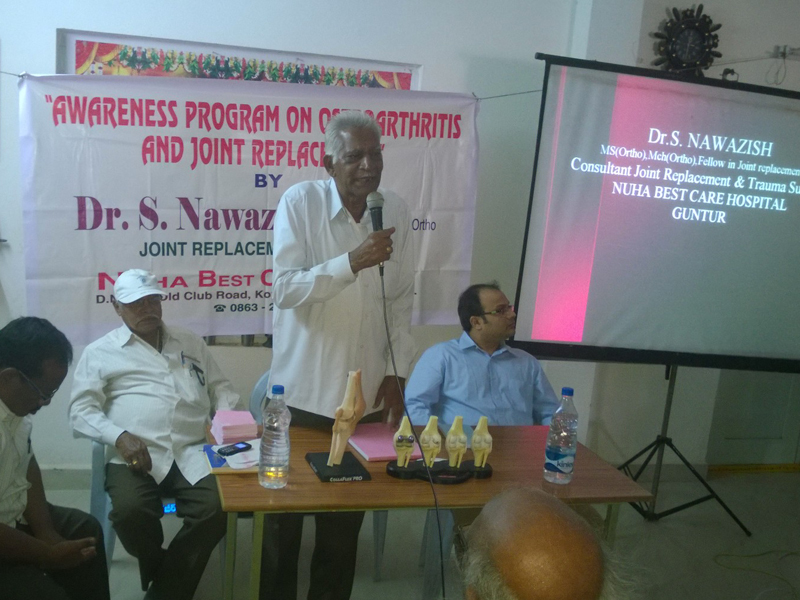

Nuha Hospital aimed to provide comprehensive, seamless and integrated healthcare services in Guntur region. Dr.Nawazish, senior orthopedician with his expertise started Nuha Hospital in 2011. He also added few more

medical services like Gynaecology & Obstetrics, Neurology and General medicine to Nuha Hospital to cater the medical needs of the people. We have a phenomenal team of doctors with international expertise committed

to provide world class standards of medical excellence.